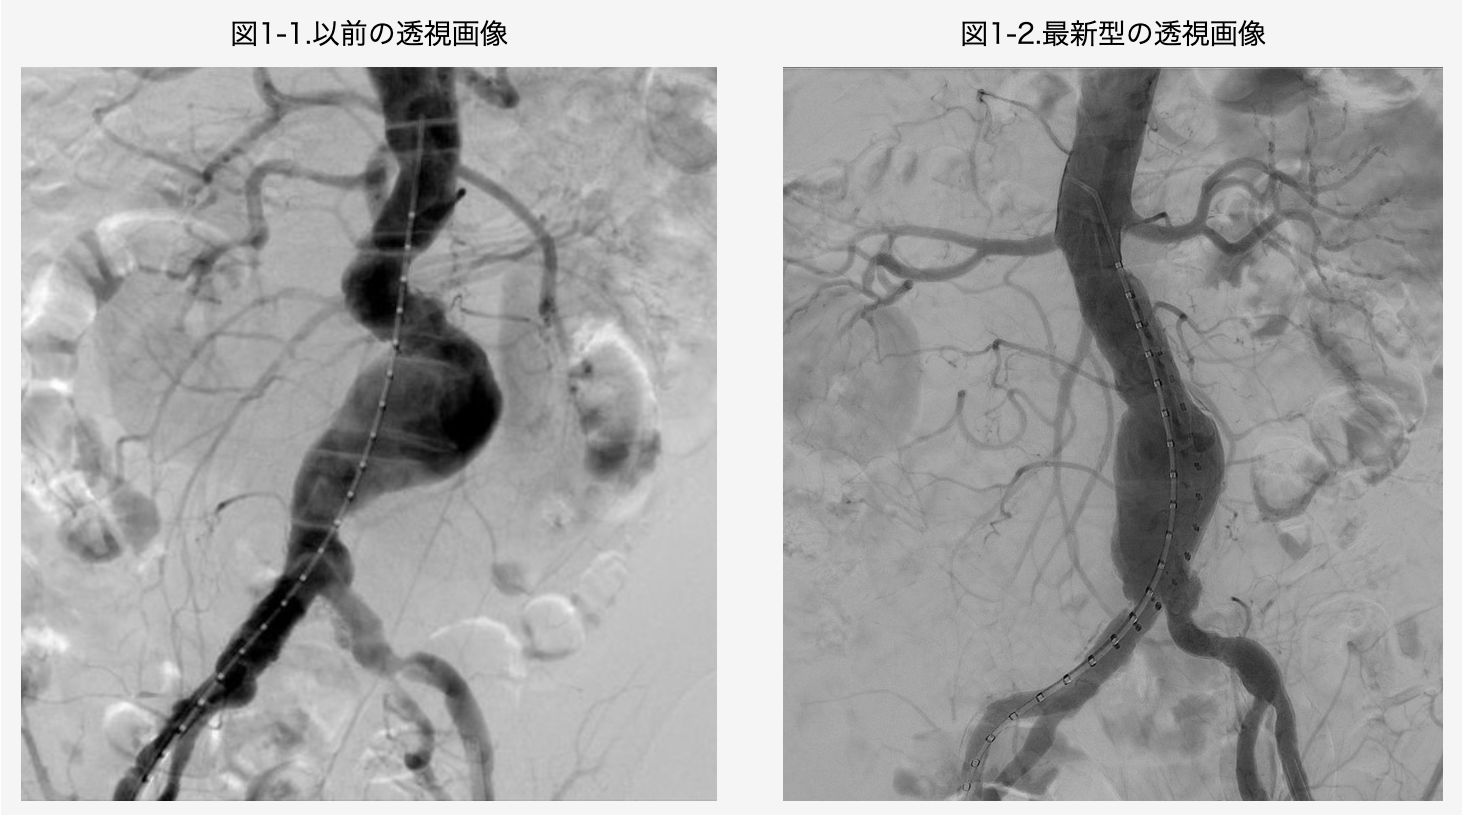

2022年末に最先端の透視装置を有する新しいハイブリッド手術室が竣工しました。画質が向上して治療の精度がさらに高まり、また低線量・低被ばくであるため、患者さんや術者に対しても優しい機器となりました。施設面でもさらなる充実を進めています。

血管撮影装置は最新の血管撮影装置を使用しており、高画質なイメージのもとで正確でレベルの高い安全な治療が可能です。さらに当科では本邦で使用可能なステントグラフト全機種の指導医資格を取得しており、病状に合わせた適切な機種選択が可能です。